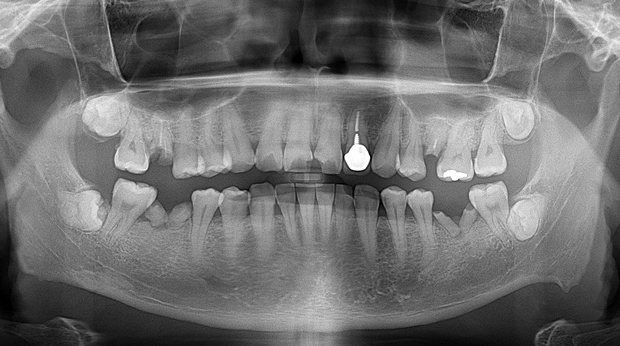

임플란트와 사랑니 발치는 외과적 시술로 잇몸을 절개하는 외과적 시술은

짧으면 짧을 수록 시술 후 붓기와 통증이 최소화됩니다.

치과의사 경력 14년차 구강외과 전문의가 빠르고 안전하게, 아프지 않게 수술해 드립니다.

치과경력 14년차 구강외과 전문의